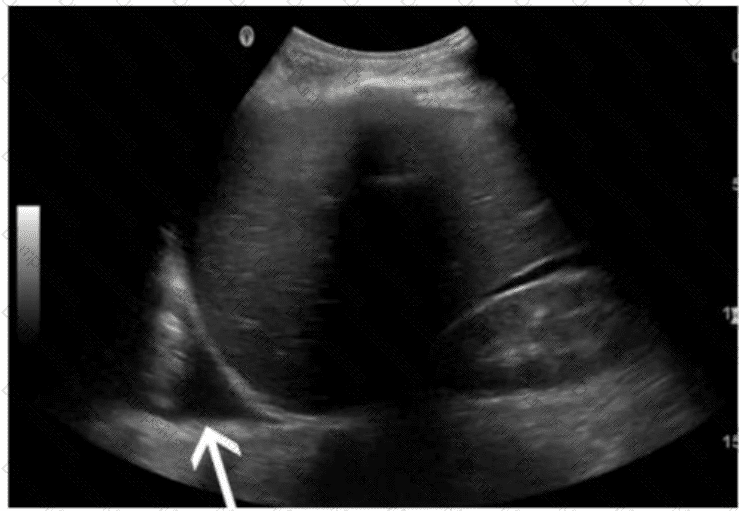

Questions 24

Which renal anomaly is demonstrated on this image?

AB-Abdomen Question 24

Options:

A.

Duplicated collecting system

B.

Crossed renal ectopia

C.

Horseshoe kidney

D.

Pelvic kidney

Buy Now